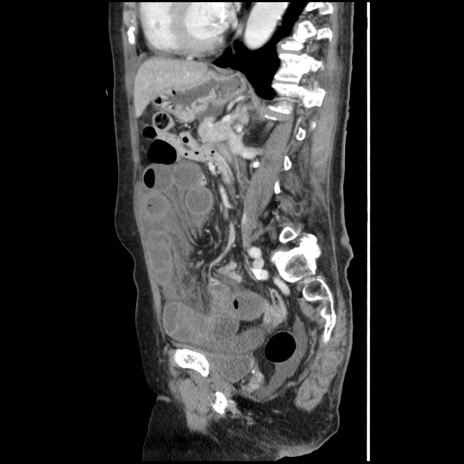

症例1(矢状断像)

【症例】80歳代女性

【主訴】腹痛

【現病歴】8時間前から腹痛あり来院。

【既往歴】糖尿病、脂質異常症、子宮体癌にて子宮全摘術

【身体所見】意識清明・会話良好だが腹痛で苦悶様、全腹部にわたって反跳痛と圧痛あり

【データ】WBC 13600、CRP 0.14、LDH 224、CK 90